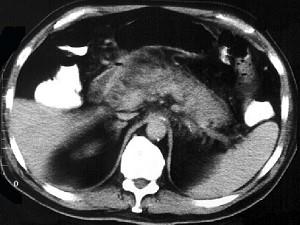

问题 男,32岁,上腹部持续性疼痛,放射至胸背部,高热,恶心呕吐,上腹部压痛反跳痛,CT检查如图,最佳的诊断是 ( )

选项 A、慢性胰腺炎急性发作 B、胰腺癌 C、出血坏死性胰腺炎 D、慢性胰腺炎 E、急性单纯性胰腺炎

答案 C